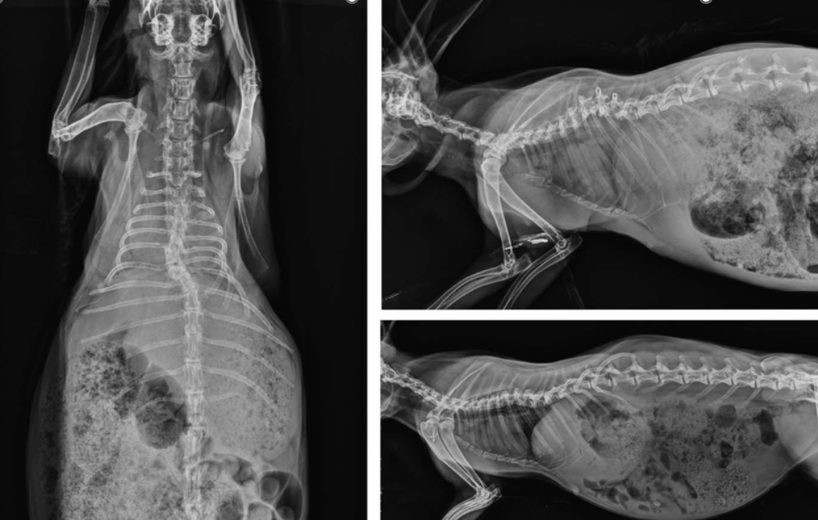

identify pathology

hyperparathyroidism in a 8 month kitten fed with sausages - image shows bendy back and sternum. - spinous processes not even visible anymore. pelvis poorly visible. - no secondary fractures yet. Can be treated with dietary change (Ca:P!!) but the bones will never return to normal.